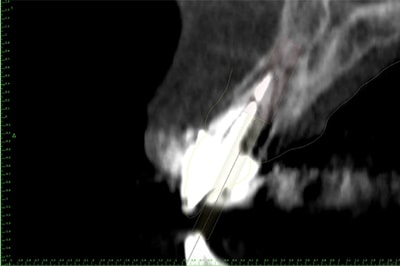

Chirurgie Guidée

L’implantologie moderne évolue vers un positionnement des implants dicté par la prothèse. Il permet et garantit un meilleur résultat esthétique, une meilleure distribution des forces et une hygiène facilitée. La combinaison de l’imagerie 3D et de logiciels de planification autorise des études préliminaires d’une grande finesse. On pourra ainsi visualiser la faisabilité prothétique d’un plan de traitement implantaire.

Au cabinet, pour les cas complexes, après réalisation d’une imagerie 3D (scanner ou cone beam), le cas sera étudié (avec un logiciel de planification), et une solution sera proposée. Dès validation, un guide chirurgical sera confectionné, dans l’absolu respect de la planification. Il permettra de positionner et placer chaque implant dans la position et l’axe pré-défini.

Plusieurs types de guides sont possibles. S’il reste des dents sur l’arcade, nous réaliserons un guide dento-porté (stable et précis). S’il ne reste aucune dent, nous devrons réaliser un guide ostéo-porté.

Ce type d’intervention permet au patient, de repartir le jour de l’intervention, avec une solution esthétique et fonctionnelle.